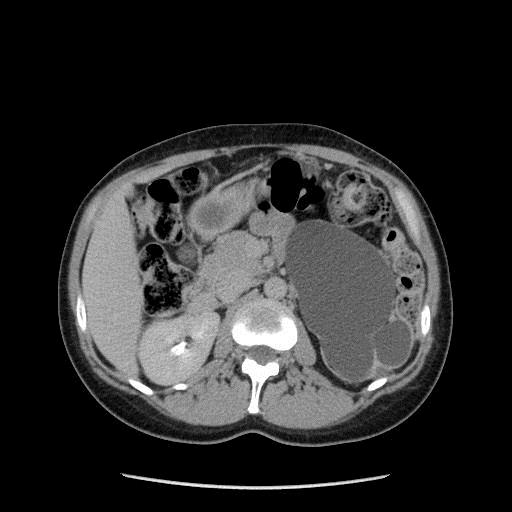

Les kystes simples sans aucun critère radiologique suspect ne nécessitent aucune surveillance ni aucun traitement sauf en cas de kyste symptomatique très volumineux responsable d’une gêne ou de douleur par compression des organes de voisinage (par exemple constipation par compression du colon). Dans ce cas les kystes peuvent être retirés sous coelioscopie.

Photo : kyste simple du rein droit